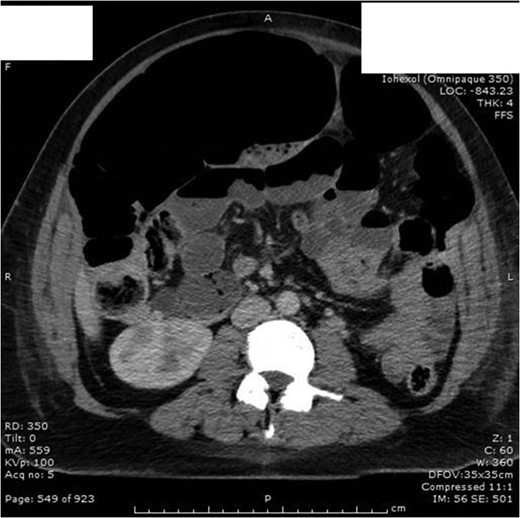

Unfortunately post laparotomy she developed ileus (Fig. 4) and laparotomy wound dehiscence. Finally 13 days post laparotomy she was discharged home with district nursing for wound management and stoma care.

Day 3 post laparotomy she developed ileus with significant gaseous distension involving the large and small bowel; with multiple air-fluid levels on horizontal beam imaging.